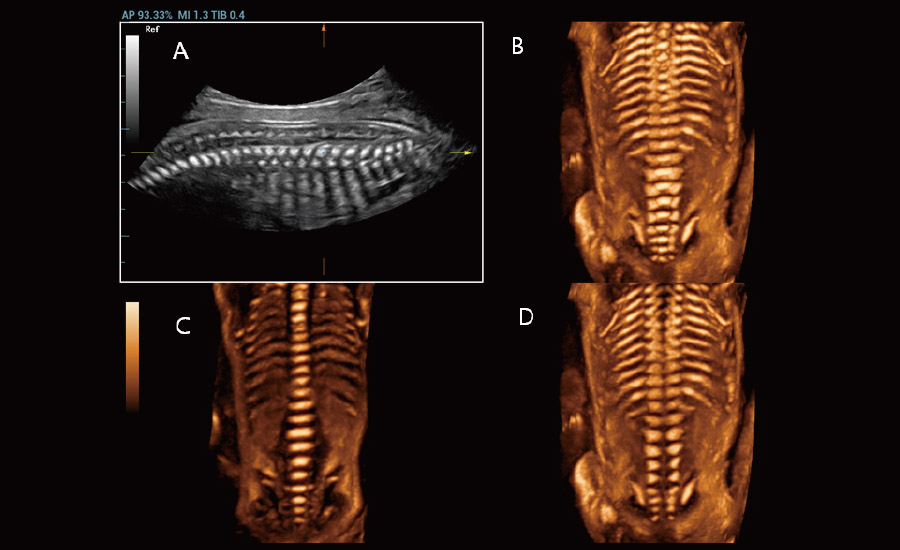

UMA (Ultra-Micro Angiography)

The innovative technology breaks the bottlenecks of traditional Doppler imaging. With ultra-high spatial resolution and flow sensitivity, it allows detecting super-subtle and super-slow flow perfusions, thereby extending the clinical application of qualitative and quantitative ultrasound evaluation in fetal brain, kidney, placenta, endometrium, ovary, etc.

UMA - fetus renal flow

3D UMA - fetus intracranial flow

Combining advanced algorithms and domain-specific knowledge, the innovative Smart Scene solution enables auto identification of tissue characteristics and provides organ-specific diagnosis with full-stack intelligence. Based on auto scenario identification, the solution not only realizes smart 2D scanning with auto settings and measurements, but also delivers 3D full-stack intelligence in every step from volume imaging optimization to the difficult 2D plane acquisition, and quantification throughout whole procedure. It helps a lot in reducing the dependency on clinical skills, while increasing diagnostic accuracy, confidence and efficiency.